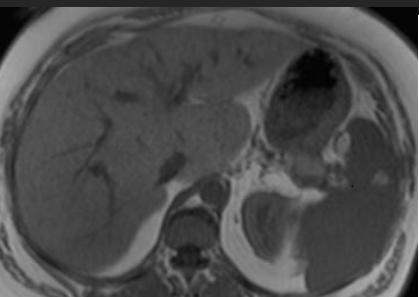

Image IRM de steatose fu foie

: Image de

hyperintense sur T1 et hypointense surT2 . L'infiltration graisseuse du foie provoque une diminution de

l'attenuation du parenchyme du foie . Sur le foie normale le

signal du parenchyme hepatique est similaire sur toutes les

images "in phase " et "opposed phase " . Dans steatose du

foie le signal du foie est hyperintense relative avec la rate (

T1 in phase ) et a opposed-phase , par la chute de

signal , image du foie est hypointensite ,

Image ỈRM normale du foie en

T1 coupe axiale .Image du foie est

hyperintense que la rate |

T2 coupe axiale . Le parenchyme du foie est moins intense que

la rate . |